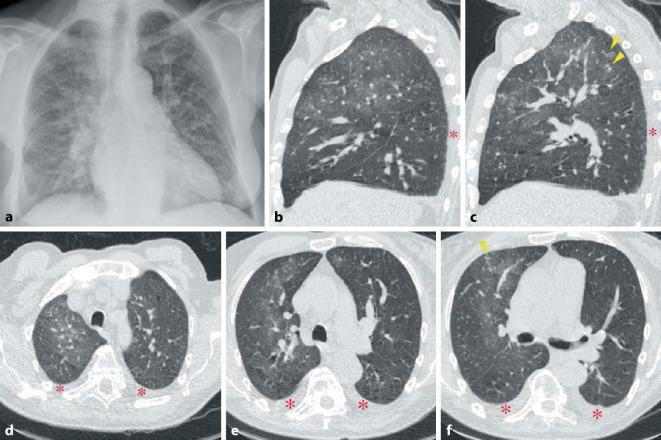

Rheumatic diseases frequently present with pulmonary involvement. All anatomic structures of the lungs can be affected. Interstitial lung diseases are characterized by a system of patterns evident in high-resolution computed tomography (HR-CT) scanning of the lungs. The HR-CT pattern can differ between rheumatic diseases.

风湿性疾病常伴有肺部受累。肺的所有解剖结构均可受到影响。间质性肺疾病的特征是在肺部高分辨率计算机断层扫描(HR-CT)中可见一系列明显的影像表现。不同风湿性疾病的HR-CT影像表现可能有所不同。

肺部受累很常见且与预后相关。肺部受累的概述显示,炎性风湿性疾病的受累解剖结构以及间质性疾病的影像表现具有高度变异性。提供了主要诊断结果的概要。

结论

此处提及的每种风湿性疾病都可能与肺部受累相关。因此,在首次诊断以及随访期间,必须进行系统的诊断评估。除了临床症状和肺功能外,肺部HR-CT对诊断起决定性作用。